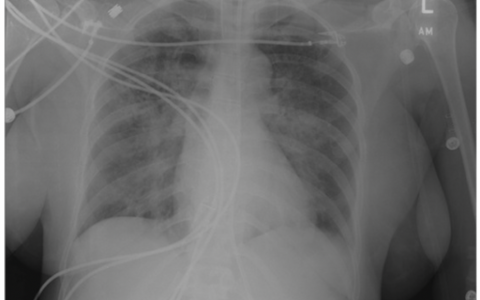

A 22-year-old woman is evaluated in the emergency department (ED) for fever, pleuritic chest pain, dyspnea, and hypotension. She was in her usual state of good health until four days ago when she developed a sore throat, nausea, and myalgia. Physical examination is remarkable for an injected pharynx without any neck tenderness or swelling. Chest radiograph reveals bilateral patchy and irregular parenchymal opacities. She is diagnosed with pneumonia and admitted to the ICU where blood cultures are obtained. Empiric treatment with piperacillin/tazobactam and azithromycin is initiated, and she is resuscitated with IV fluids. Chest CT demonstrates right-sided pleural effusion and multiple cavitary and nodular opacities consistent with septic emboli. The next day, her blood cultures grow Fusobacterium necrophorum, and antibiotic therapy is narrowed down to piperacillin/tazobactam.

肺部并发症很常见。肺部病变通常表现为脓毒性肺栓子引起的坏死空洞性病变。大关节是脓毒性栓塞累及的第二常见部位,仅次于肺部。26%的患者有关节受累(最常累及膝关节和髋关节)。中枢神经系统受累已有报道,但不常见。报道的中枢神经系统并发症包括脑膜炎、脑脓肿、硬膜下积脓、硬膜外脓肿、脓毒性栓子和脑梗死。脑静脉血栓形成也有报道,据推测是由颈内静脉血栓的逆行延伸所致。